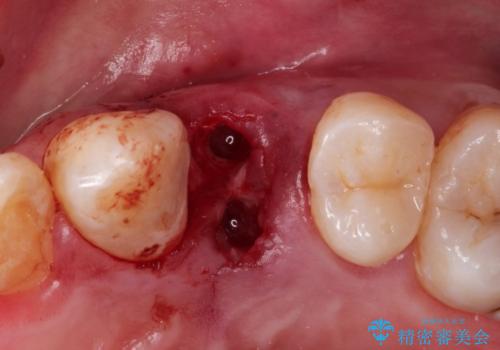

虫歯がかなり進行していて根っこしか残っていない状態でした。日々の歯ブラシが上手く出来ていなくプラーク(細菌の塊)も溜まっている状態でした。

歯を保存するのは出来ないと診断し抜歯した後にインプラントで治療を行いました。

長い間虫歯を放置していたため、根っこだけになっている状態でした。このままでは被せ物を被せられないため抜歯を行い治癒を待った後にインプラントを埋入しオールセラミッククラウンで治療を行いました。